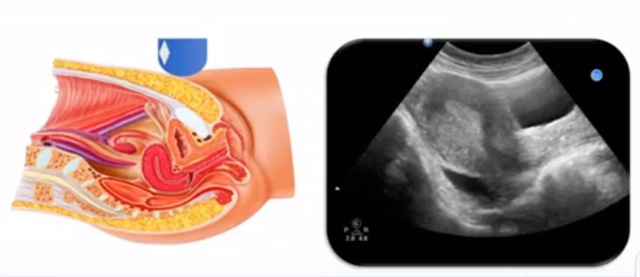

女性生殖系統(tǒng)包括內(nèi)、外生殖器官及其相關(guān)組織以及鄰近器官,其中內(nèi)生殖器是我們超聲檢查的主要對象。那么內(nèi)生殖器包括陰道、子宮還有輸卵管及卵巢。輸卵管及卵巢稱為子宮附件。子宮是倒置梨形,但是它是空腔厚壁肌性器官。它的正常值在育齡婦女。超聲探頭放在貼近腹壁盆腔上面位置,來看這個(gè)子宮在超聲上面的表現(xiàn)。從輪廓上來講,和示意圖是一樣的。這就是在超聲上面顯示的一個(gè)子宮的圖片。子宮在不同的時(shí)期與子宮頸的比例。成年婦女指的是育齡婦女為2:1子宮體是比較大的,嬰兒期為1:2說明宮頸比較大,絕經(jīng)期1:1。所以我們在看到子宮圖時(shí)候可以根據(jù)宮體宮頸比例大致可以推測屬于哪個(gè)時(shí)期的婦女。另外還可以根據(jù)比例大小來推斷是一個(gè)正常子宮還是異常子宮。

子宮從外到內(nèi),漿膜層、肌層、粘膜層。宮體部宮頸為梭形結(jié)構(gòu)。宮腔為上寬下窄的三角形,連接為峽部。子宮有什么功能呢?月經(jīng)血產(chǎn)生跟排出通道,精子運(yùn)行通道受精作用。囊胚著床及胎兒發(fā)育、生長的場所。分娩時(shí)產(chǎn)生宮縮使胎兒、胎盤娩出。未孕的子宮是很小的,已孕子宮就非常大,平均胎兒都有6斤重。所以這個(gè)后壁就體現(xiàn)出來。輸卵管由子宮角部向外延伸,為一對細(xì)長而彎曲的管道,呈管狀中空結(jié)構(gòu),大概長度是8-14厘米,粗1-4毫米,它的下方為卵巢和闊韌帶。間質(zhì)部是厚一點(diǎn)的,峽部是比較窄的地方,壺腹部,漏斗部。正常情況下,輸卵管在普通超聲DR難以顯示。